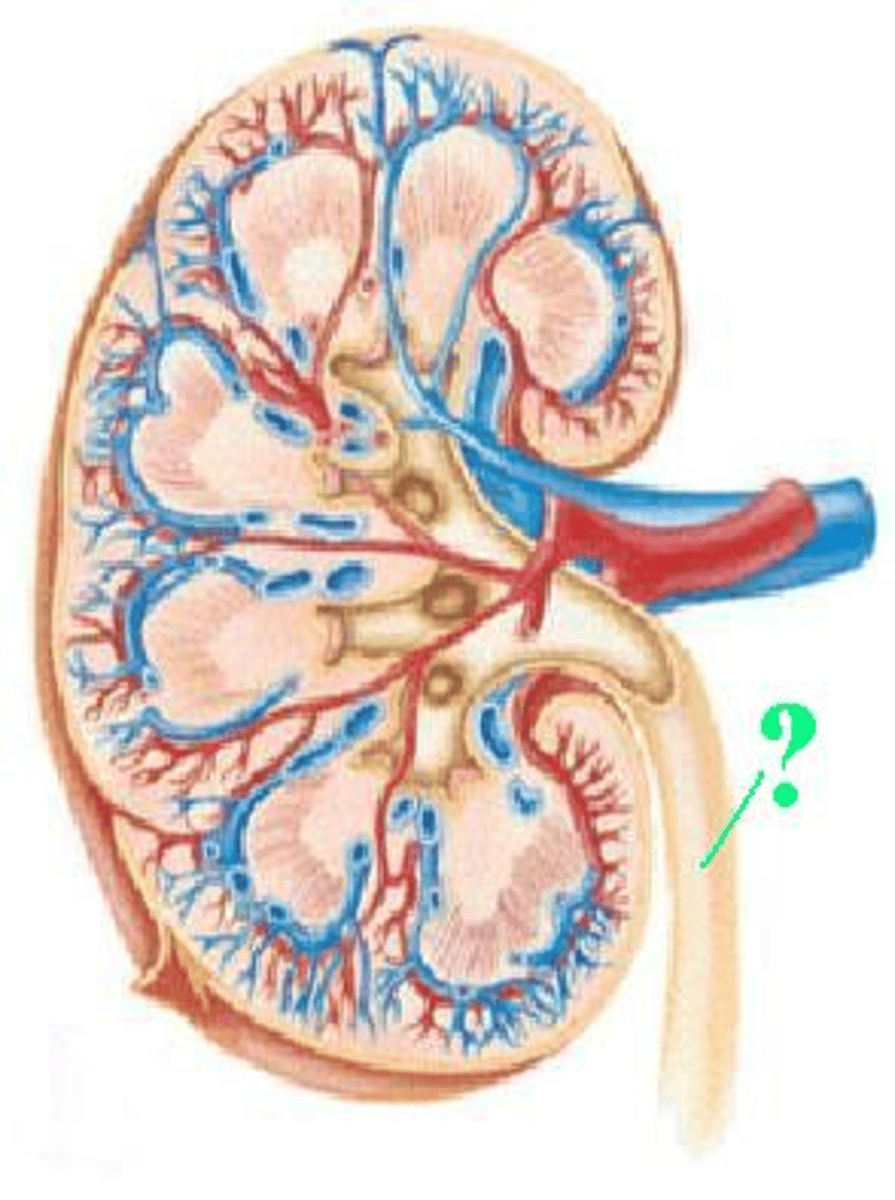

renal vein

What is the vessel that drains blood from the kidney called?

Identify the indicated vessel.